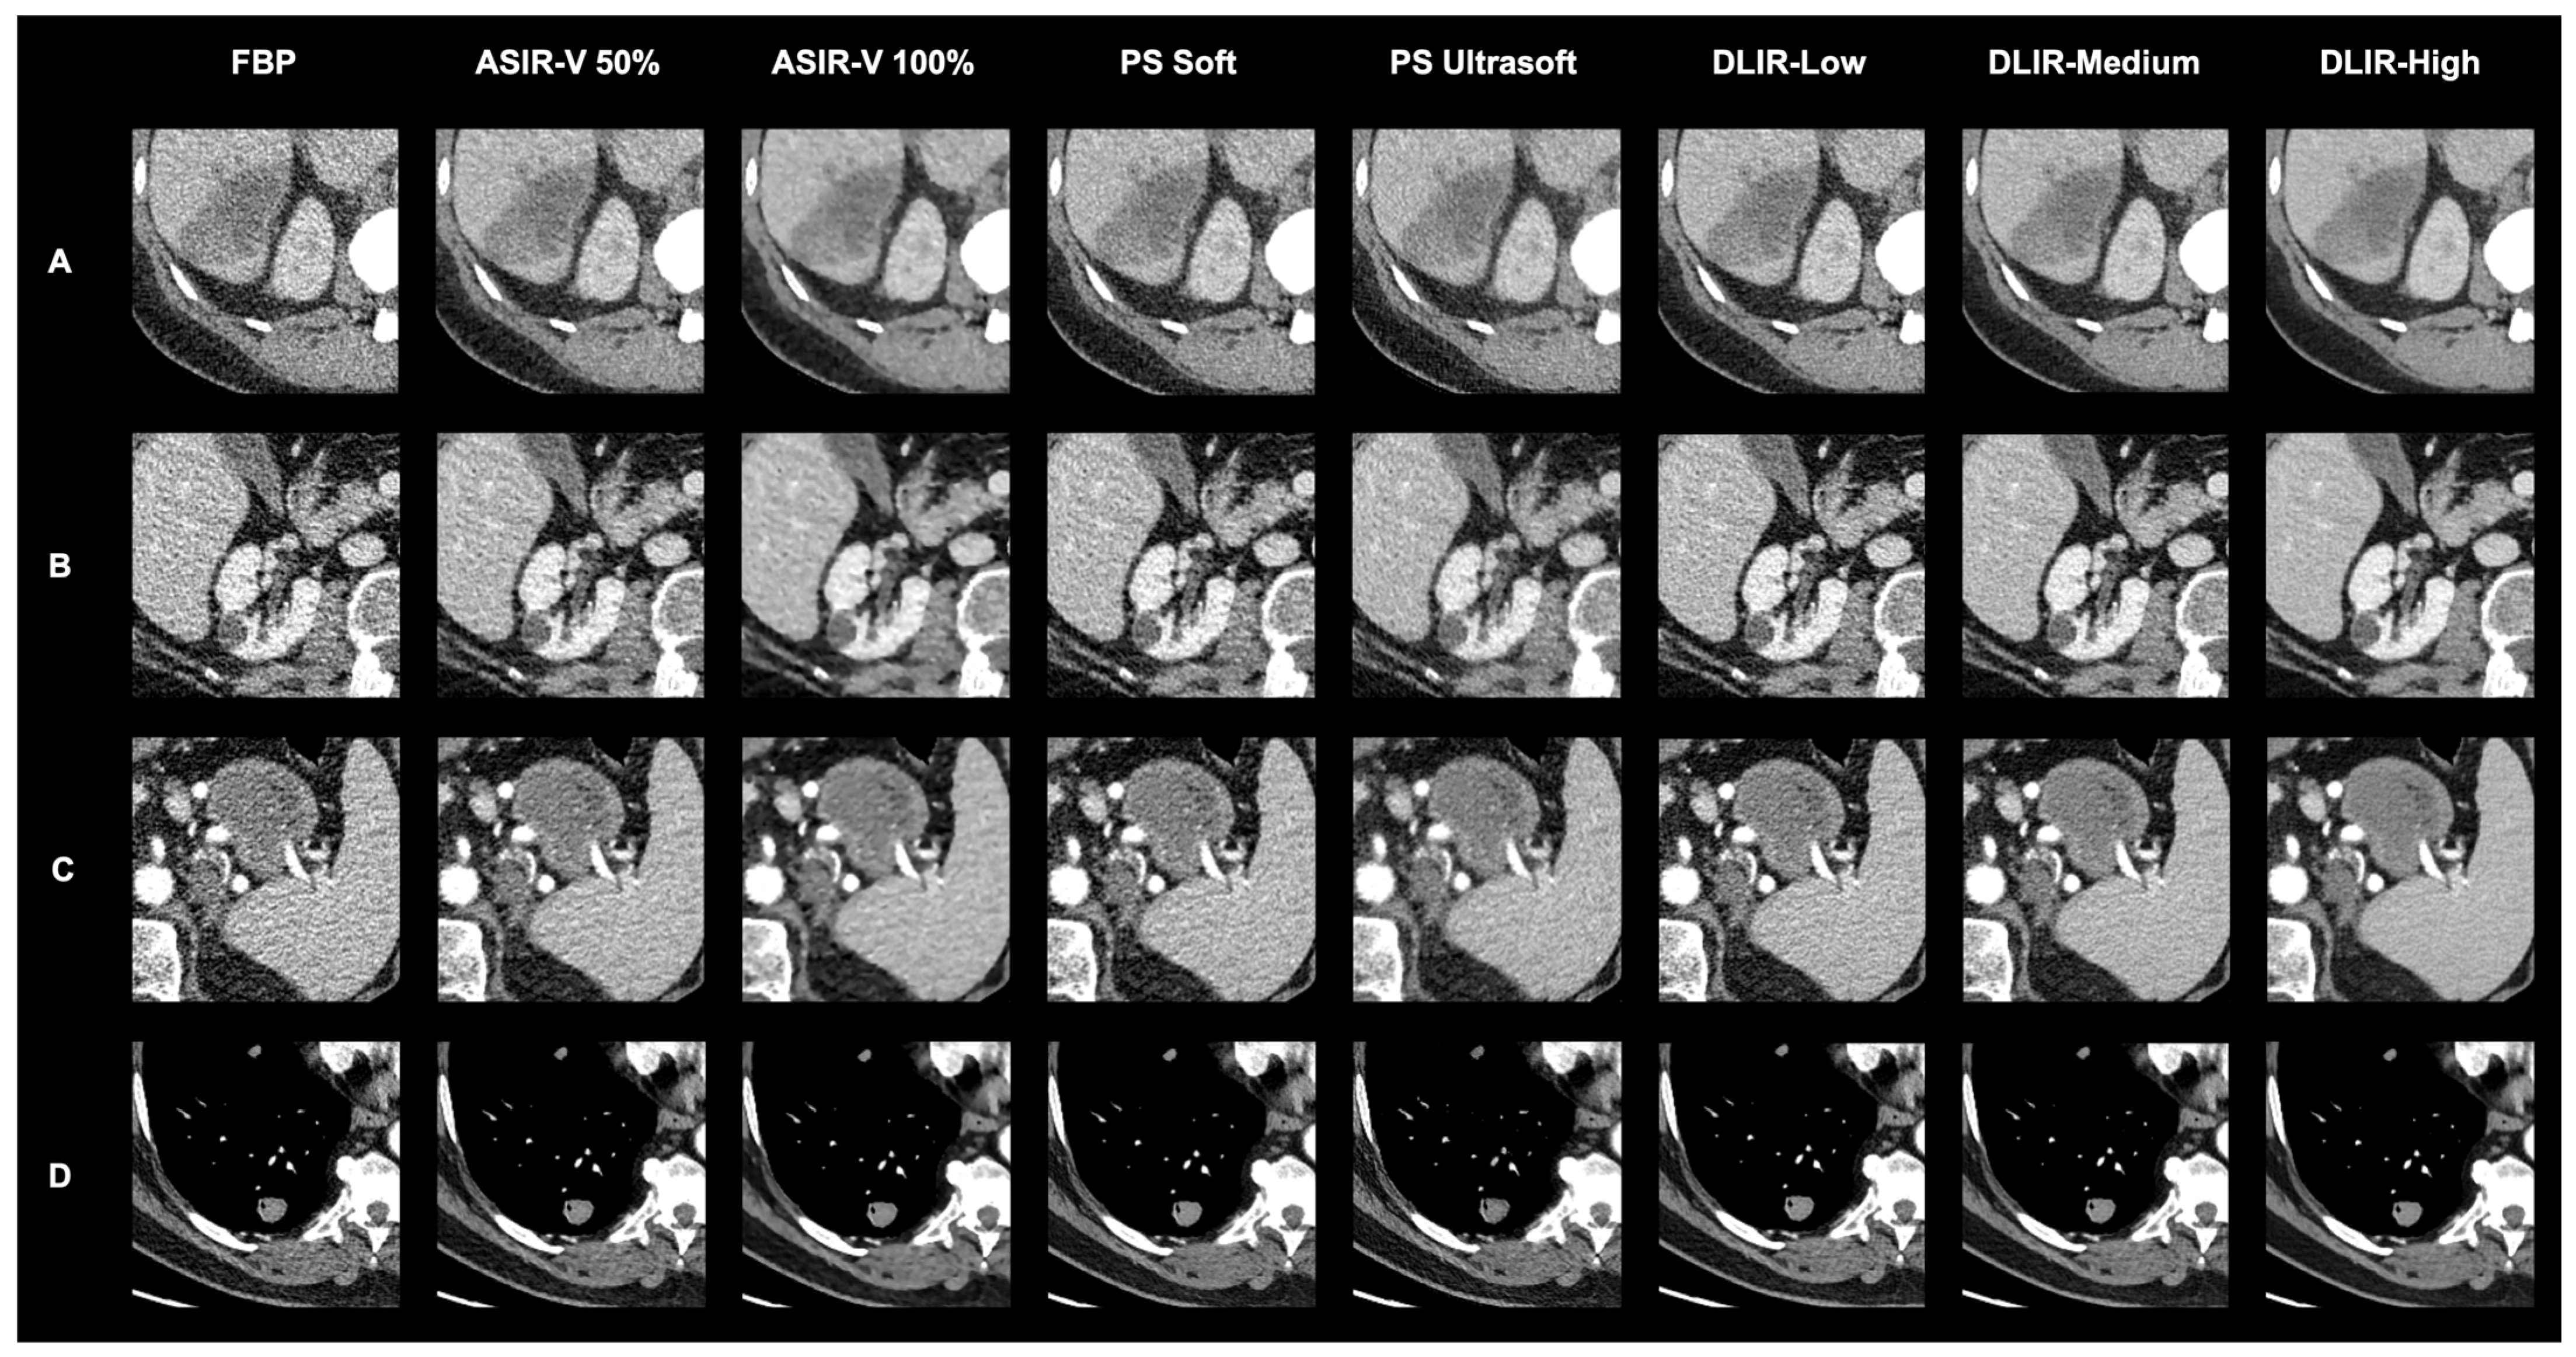

| This study | 28 | 0–17 | 33 | chest, abdomen and pelvis staging | art. and pv. | - GE Revolution with stagging protocol (voltage: 120 kVp, slice thickness 0.625 mm) - Reconstructions: FBP, ASIR-V (30%, 50%, 70%, 100%), Pixelshine (Soft, Ultrasoft), DLIR (High, Medium, Low) - Evaluation: qualitative analysis of ranked image quality on a scale from 1 (best) to 8 (worst); qualitative analysis of image interpretation, structural differentiability, and diagnostic certainty for ASIR-V 50%, ASIR-V 100% DLIR-High and DLIR-Low using a 5-point Likert scale; quantitative analysis of SNR and CNR | - Qualitative: DLIR-High ranked highest, followed by DLIR-Medium and DLIR-Low; ASIR-V 50%, Pixelshine Soft, and Ultrasoft were mid-ranked, with FBP and ASIR-V 100% at the bottom; DLIR-High is preferred for all three criteria (image interpretation, diagnostic certainty, and structural differentiability), followed by DLIR-Low, ASIR-V 50%, and ASIR-V 100%. - No significant difference in evaluation between younger and older radiologists, or between arterial and portal venous phases. - Quantitative: SNR and CNR (best to worst)—DLIR-High = ASIR-V 100%, DLIR-Medium = ASIR-V 70%, DLIR-Low = PS Ultrasoft = ASIR-V 50%, PS Soft, ASIR-V 30%, FBP; DLIR-High and ASIR-V 100% showed the highest SNR- and CNR-values with the lowest noise. |